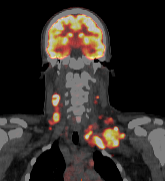

High-sensitivity PET scan fused with low-dose CT scan.

The PET scan is placed over the CT scan to show how the tracer compound is absorbed by the body. Areas that use high amounts of glucose (sugar), like the brain, appear brigher. Images provided courtesy of GE.